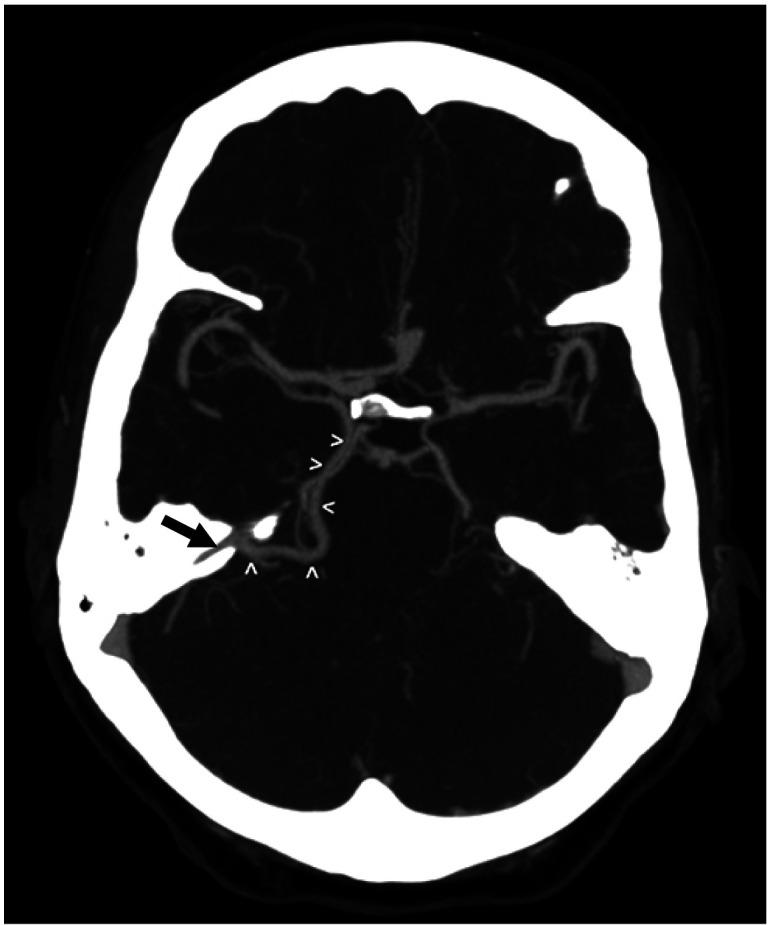

An adult male was found to have a variation of the left basal vein of Rosenthal after presenting with complaints of headache and balance issues. In this case, the vein drained directly into the left superior petrosal sinus (SPS) instead of the great vein of Galen. Anatomical variation of the basal vein is likely due to embryonic development of the deep cerebral venous system as primitive structures either differentiate regress or further with age. These changes may result in the uncommon presentation seen in this case. To our knowledge, this is the first case that shows the basal vein drains into the SPS. The normal and variant anatomy of this vessel are discussed.

一名成年男性在出现头痛和平衡问题后,被发现存在罗森塔尔左基底静脉变异。在该病例中,该静脉直接汇入左岩上窦(SPS),而非大脑大静脉。基底静脉的解剖变异可能归因于大脑深部静脉系统的胚胎发育,随着年龄增长,原始结构要么分化、退化,要么进一步发育。这些变化可能导致了本病例中所见到的罕见表现。据我们所知,这是首例显示基底静脉汇入岩上窦的病例。本文讨论了该血管的正常和变异解剖结构。